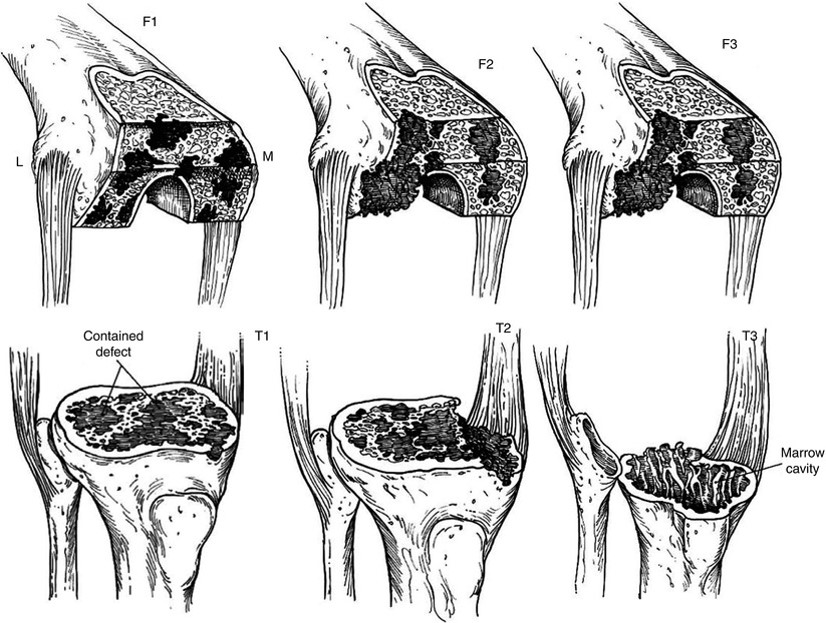

В своїй роботі ми користувалися класифікацією кісткових дефектів ложе нестабільного протеза колінного суглоба за AORI (Anderson Orthopaedic Research Institute, USA), 1997 де автори виділяють 3 типа кісткових дефектів

Тип 1 – інтактна кістка (intact metaphysealbone) – невеликі кісткові дефекти, зазвичай без пошкодження кортикальної кістки. Характеризується нормальною кісткової структурою і збереженням губчастої і кортикальної кістки метафиза, нормальним рівнем суглобової лінії. позначаються як F1 – для стегнової кістки і Т1 – для великогомілкової.

Тип 2 – пошкоджена кістка (damаged metaphyseal bone) – характеризується втратою губчастої і кортикальної кісткової маси метаепіфізів, без заповнення якої неможливе створення надійної опори для компонентів ревізійного імплантату і відновлення анатомічного рівня суглобової лінії. (F2 А та F2 Б – для стегнової і Т2 А та Т2 Б – для великогомілкової кісток)

Тип 3 – дефіцит кістки (deficient metaphyseal segment) – характеризується вираженою втратою губчастої і кортикальної кісткової маси метаепіфіза, без компенсації якої неможливе створення опори для компонентів ревізіційного імплантату і відновлення нормального рівня суглобової лінії. Дефекти частіше поширюються до надвиростків і вище на стегнової кістці або до горбистості  і нижче на великогомілковій кістці. (F3 А та F3 Б – для стегнової і Т3 А та Т3 Б– для великогомілкової кісток)